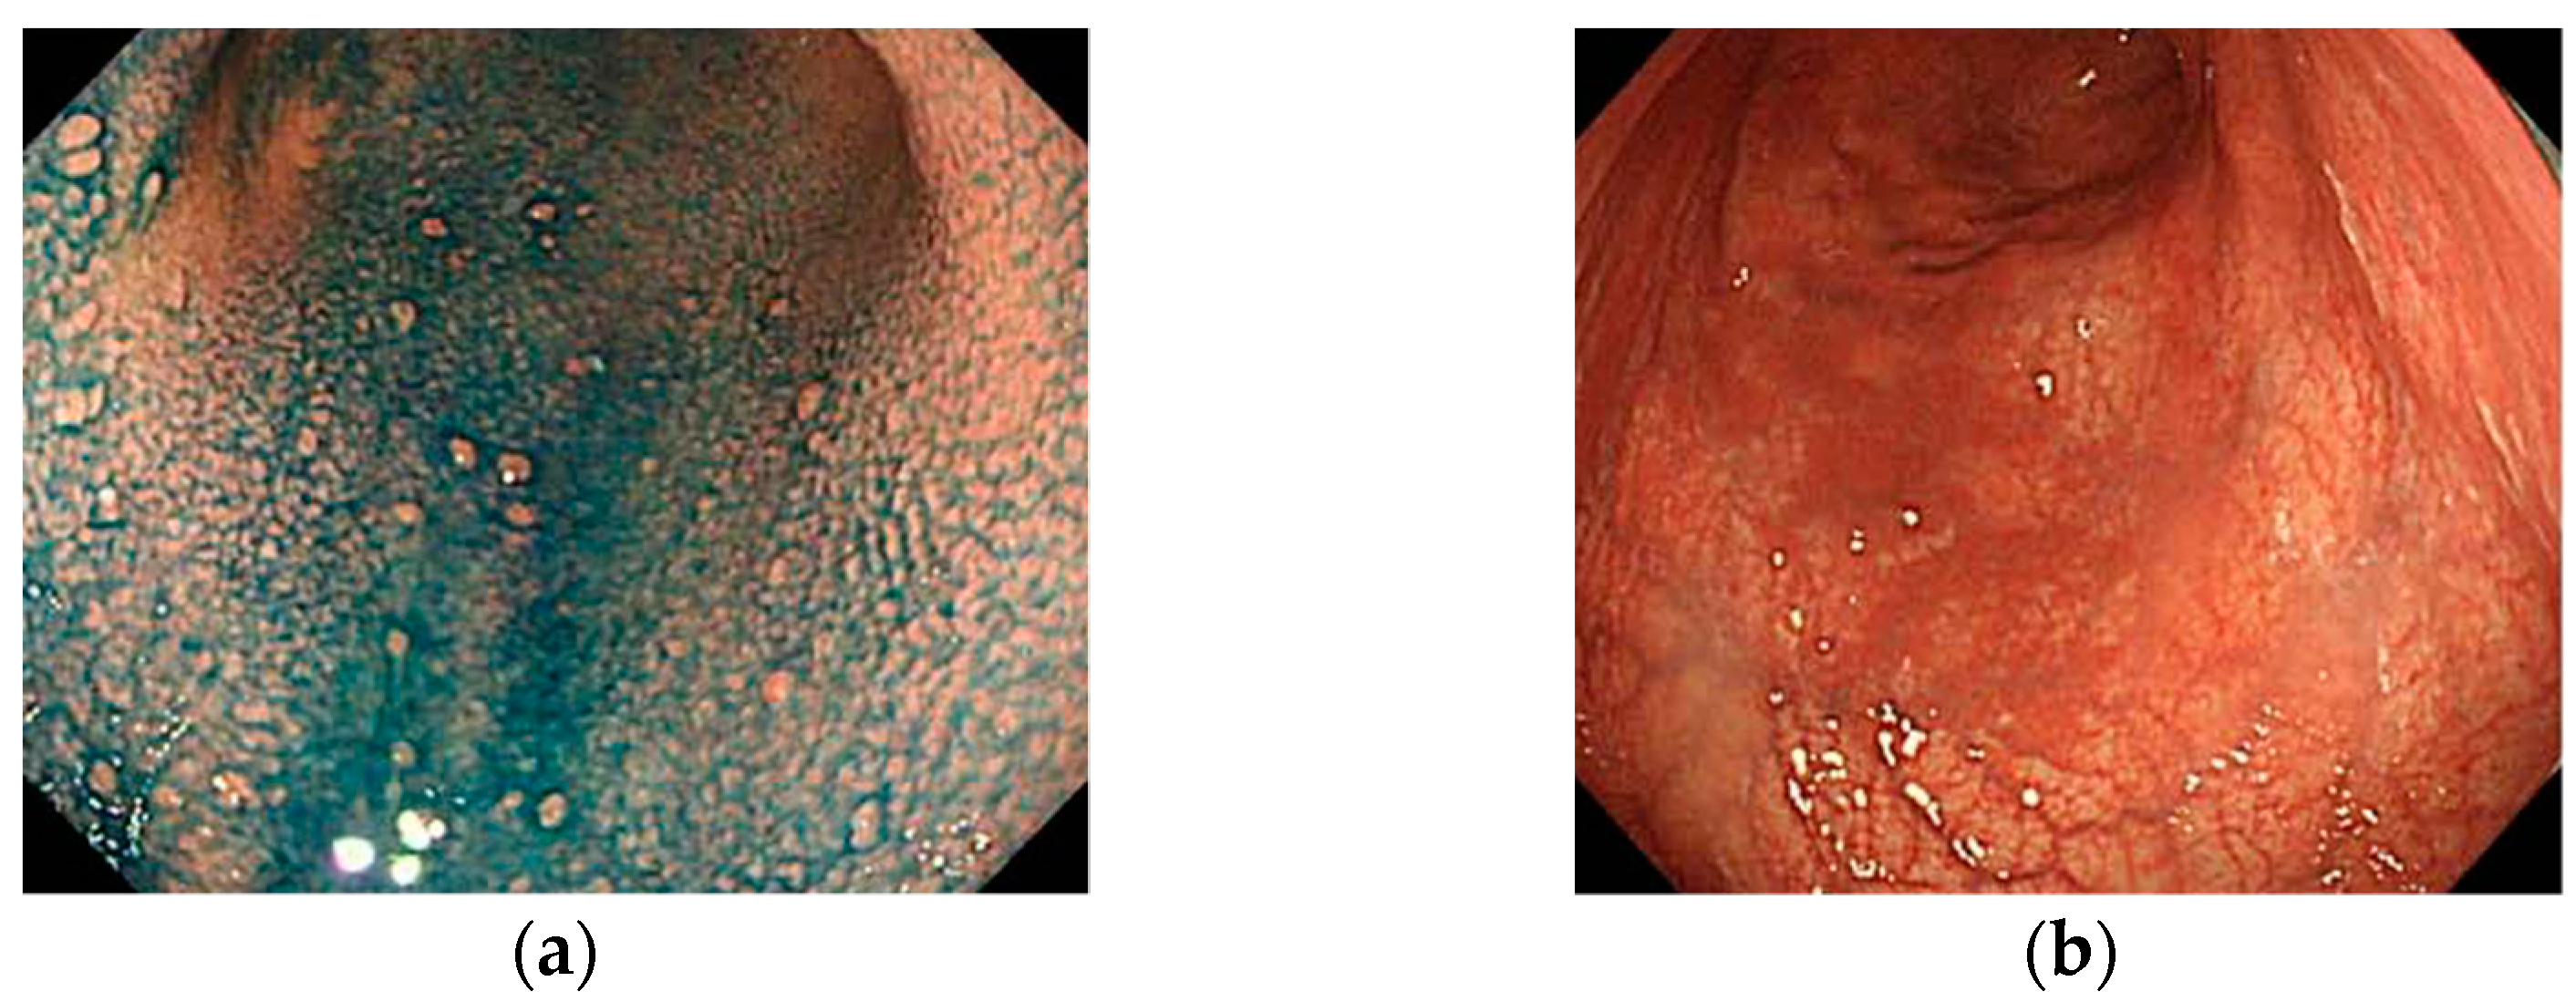

4.2.2. Findings via IEE

5. Findings of Early AIG

- Yagi, K.; Nakamura, A.; Sekine, A.; Graham, D. Features of the atrophic corpus mucosa in three cases of autoimmune gastritis revealed by magnifying endoscopy. Case Rep. Med. 2012, 2012, 368160. [Google Scholar] [CrossRef] [PubMed] [Green Version]

- Maruyama, Y.; Yoshii, M.; Kageoka, M. Features of magnifying endoscopic findings in type A gastritis. Stomach Intest. 2018, 53, 1516–1521. (In Japanese) [Google Scholar]

- Kato, M.; Uedo, N.; Toth, E.; Shichijo, S.; Maekawa, A.; Kanesaka, T.; Takeuchi, Y.; Yamamoto, S.; Higashino, K.; Ishihara, R.; et al. Differences in image-enhanced endoscopic findings between Helicobacter pylori-associated and autoimmune gastritis. Endosc. Int. Open 2021, 9, E22–E30. [Google Scholar] [CrossRef] [PubMed]

- Kanzaki, H.; Uedo, N.; Ishihara, R.; Nagai, K.; Matsui, F.; Ohta, T.; Hanafusa, M.; Hanaoka, N.; Takeuchi, Y.; Higashino, K.; et al. Comprehensive investigation of areae gastricae pattern in gastric corpus using magnifying narrow band imaging endoscopy in patients with chronic atrophic fundic gastritis. Helicobacter 2012, 17, 224–231. [Google Scholar] [CrossRef] [Green Version]